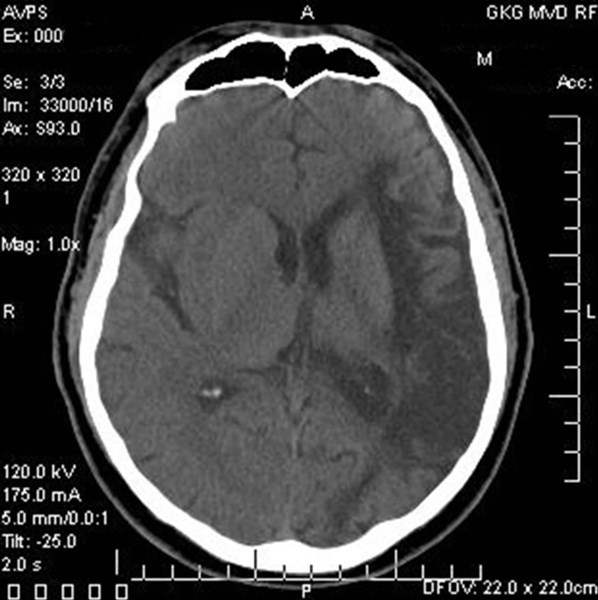

The mobile stroke treatment unit looks like an ambulance but is more like a specialized emergency department on wheels, designed to deliver expert stroke care to the patient in the community. The MSTU will carry a CT scanner, lab testing, a critical care-trained nurse, and telestroke equipment on board that allows for remote evaluation of the patient and review of the brain scan by a stroke neurologist. If the specialists determine the patient is truly having a stroke, treatment with clot-busting medicine (t-PA) can immediately begin at the scene or en route to the hospital.